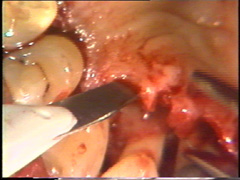

Aquí el defecto en la superficie de la raíz del central es claramente visible. Todo el tejido de granulación ha sido eliminado y el cráter óseo fué remodelado. El colgajo debe ser ubicado apilcalmente al defecto de la raíz para evitar la acumulación de placa subgingival postoperatoria.

En las regiones dónde la morfología ósea impide un cierre adecuado del colgajo, se realizan recortes menores de la configuración del hueso. En este caso particular el  hueso de la superficie bucal del segundo premolar impide una adaptación del colgajo. El hueso es remodelado con un cincel, con golpes cortos y suaves. Este instrumento es preferible al uso del instrumental rotatorio, porque son más difíciles de controlar y la visión del profesional se entorpece por el uso necesario del refrigerante acuoso.